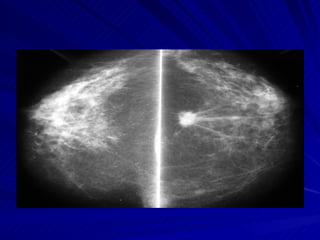

Mamografía normal

Mama normal  superior   Mediolateral  externo  Craneocaudal